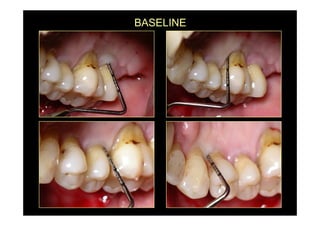

baseline

Baseline radiograph

Preoperative pocket depth

Access flap surgery

EMD application and suturing

Postoperative radiograph